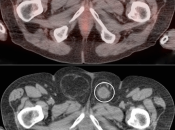

Bladder Hernia

While the CT appearance of this finding should never be missed, its striking PET appearance has led more than one PET/CT reader astray.

Usually, the supero-lateral margin of the bladder will be seen partially entering the inguinal canal. Occasionally, a significant segment of the bladder may extend deep into the hernia defect.

Caveat: Never be duped by an unusual focus of intense metabolic activity anywhere in the body. Always rule out every possible non-neoplastic explanation before raising the specter of cancer.